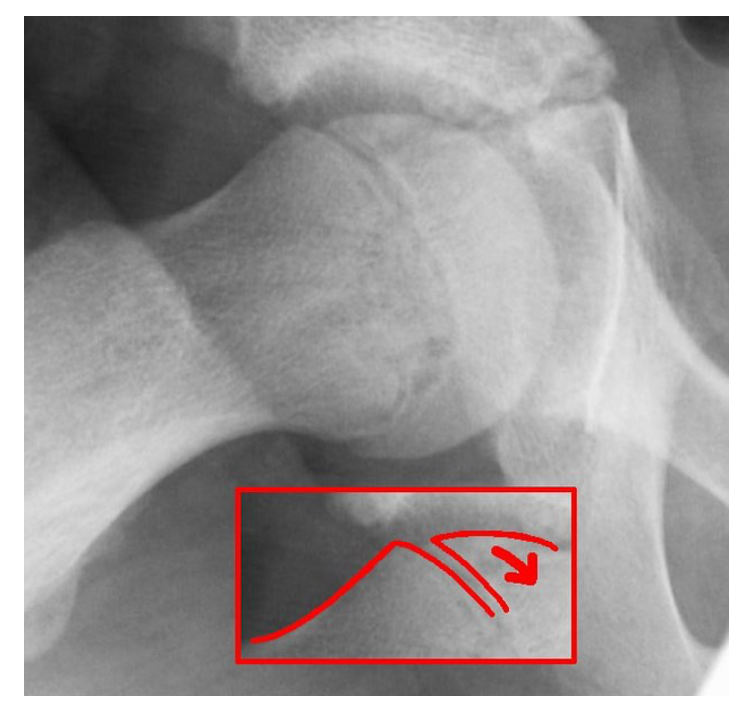

Slipped Upper Femoral Epiphysis (SUFE)

This is a hip condition which occurs when the epiphysis slips off the femoral head

– X-ray: AP and lateral (frog-leg) views shows displacement of epiphysis

Image 1: Dr. Jochen Lengerke, CC0, via Wikimedia Commons